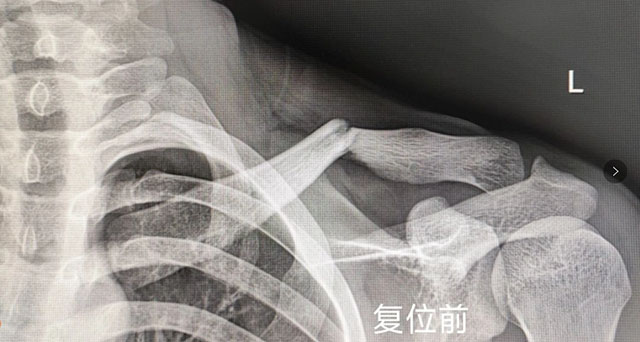

【围观】时隔一年,泸州又一“爬树哥”遭了

CT复查显示复位成功,不需手术去年12月,泸州一男子爬树时被树枝挂住衣服,从树上跌落,肩部外侧着地导致锁骨骨折。在西南医科大学附属中医医院骨伤科创伤·正骨组经中医正骨手法复位,1月完全恢复。2024年10月2日,泸州又一“爬树哥”从树上跌落...